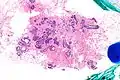

| Very low magnification micrograph of atypical ductal hyperplasia (ADH). The piece with ADH was circled by the pathologist with a marker, as it is so small, and sent for an additional opinion. H&E stain. | |

Atypical ductal hyperplasia (ADH) is the term used for a benign lesion of the breast that indicates an increased risk of breast cancer.[1]

The name of the entity is descriptive of the lesion; ADH is characterized by cellular proliferation (hyperplasia) within one or two breast ducts and (histomorphologic) architectural abnormalities, i.e. the cells are arranged in an abnormal or atypical way, more so than usual ductal hyperplasia.

ADH, cytologically, architecturally and on a molecular basis, is identical to a low-grade ductal carcinoma in situ (DCIS);[3] however, it has a limited extent, i.e. is present in a very small amount (< 2 mm).